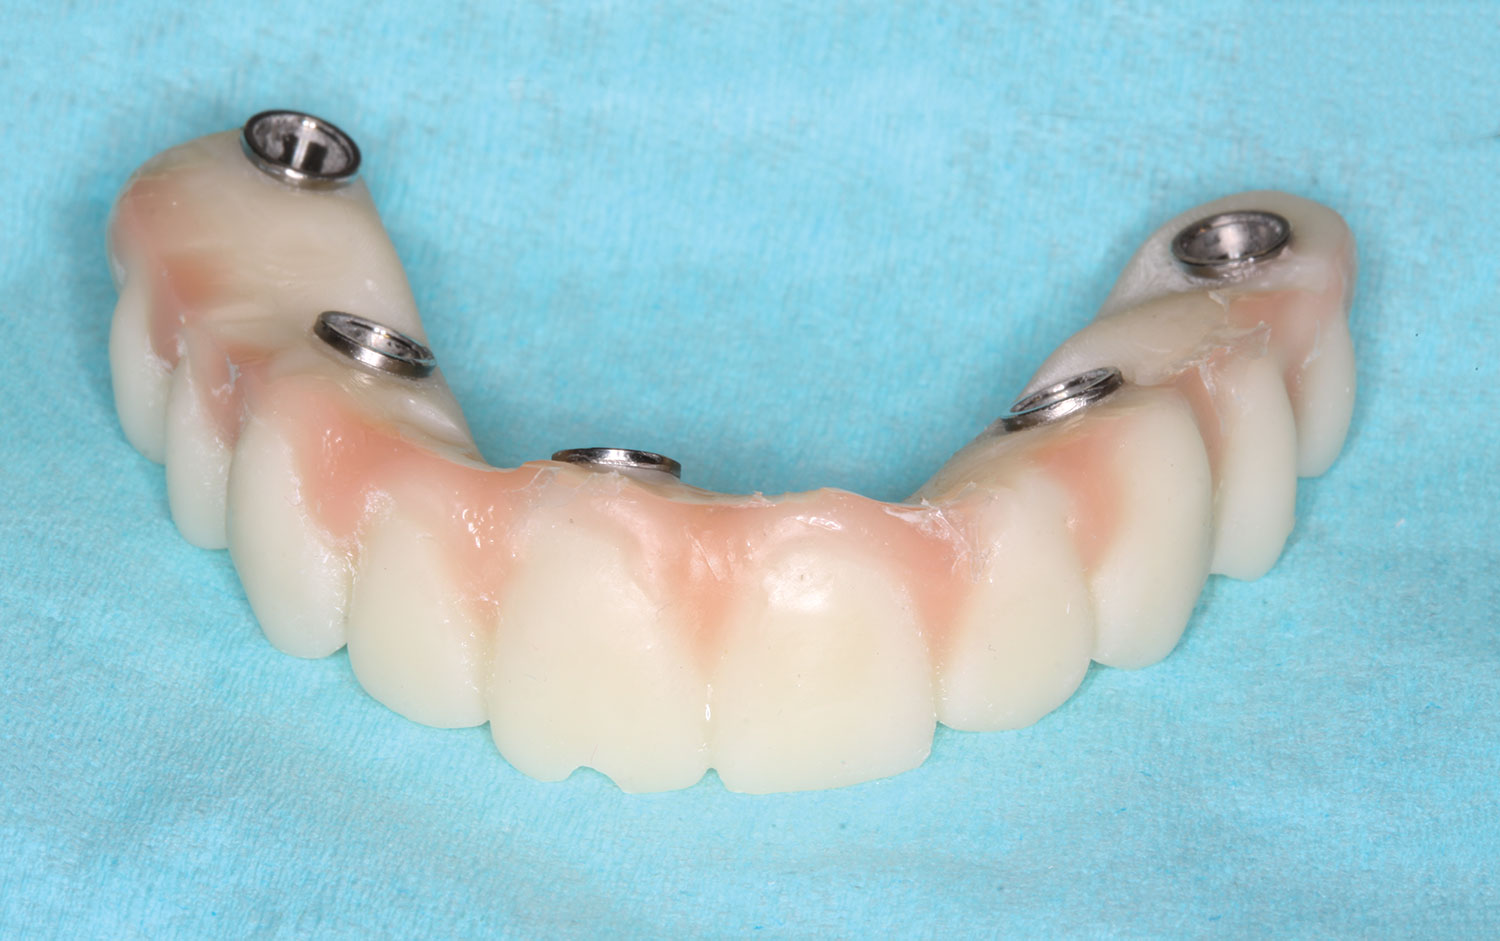

The implant company then returned an STL design file electronically via email. The office staff sent this file to the practice's 3D printer, and the appropriate color nanoceramic resin was used to print the prosthesis at 100 microns. Next, metal titanium (ti)-base cylinders, made specifically for the multi-unit abutments, were inserted into the prosthesis, which was then stained and glazed, and gingival color was applied to establish optimum esthetics (Figure 5).

Fig 5. Maxillary provisional prosthesis printed and ti-bases inserted.

Figure 5

Fig 16. Maxillary provisional prosthesis printed and ti-bases inserted.

Figure 16

Fig 31. Mandibular provisional prosthesis printed demonstrating screw-access holes in prosthetically correct positions.

Figure 31

Fig 37. Display of prosthetically correct screw-access channels in maxillary provisional prosthesis.

Figure 37